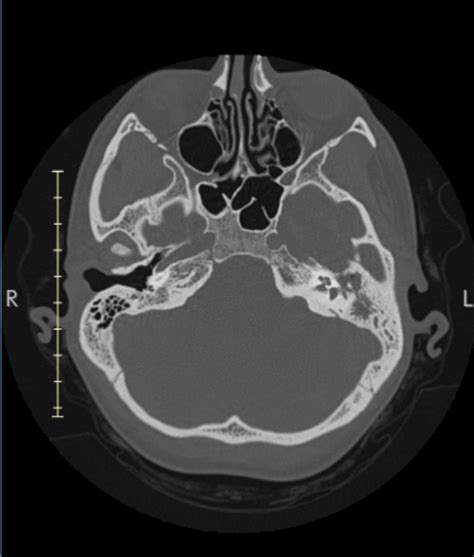

Because the mastoid air cells are deeply embedded within the skull, they cannot be seen through a standard physical ear examination. Instead, doctors rely on advanced imaging techniques to assess their health and structure. These imaging tools are essential for diagnosing conditions like chronic ear infections, mastoiditis, or detecting anatomical abnormalities.

Computed Tomography (CT) Scan The gold standard for visualizing the bony structure and identifying fluid or infection in the air cells.

When the mastoid air cells become inflamed or infected, it is referred to as mastoiditis. This often occurs when a middle ear infection spreads into the surrounding mastoid bone. Because these air cells are interconnected, bacteria can easily travel from the middle ear into the mastoid, turning a contained infection into a more serious, systemic concern.